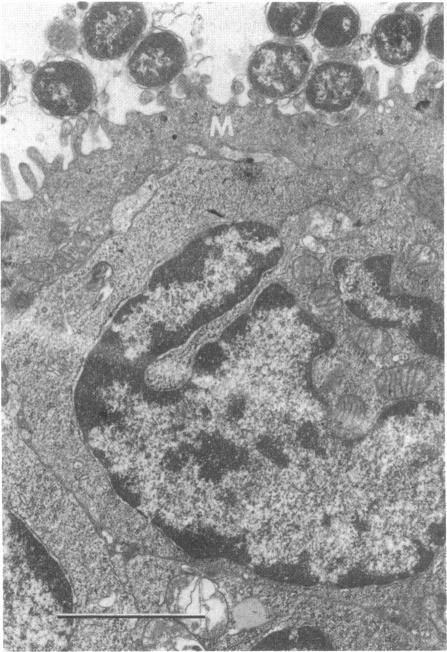

Escherichia coli (strain RDEC-1) adheres to M cells of rabbit Peyer's patch lymphoid follicle epithelium. The RDEC-1 strain contains an 85 X 10(6) D plasmid that codes for pili, which, when purified, adhere to gut absorptive epithelium. This study compared the in vivo lymphoid follicle adherence of the RDEC-1 strain with that of a Shigella flexneri (ShD15) that contained the 85 X 10(6) D plasmid and expressed the RDEC-1 pili, a control E. coli, and a control S. flexneri (ShD12). The bacteria were given in a dose of 10(10) to 0.7-1.1 kg rabbits. The rabbits were sacrificed at 2, 4, 6, and 12 h postinoculation. Peyer's patch tissue was examined by electronmicroscopy and direct fluorescence microscopy. The piliated ShD15 and RDEC-1 bacteria adhered in large numbers at 2 and 4 h postinoculation, but only the RDEC-1 strain persisted and increased in numbers past that time. Control strains did not adhere. The ShD15 strain adhered to and was rapidly taken into M cells, precipitating an acute inflammatory reaction within the follicle and adjacent lumen. Initial lymphoid follicle M cell adherence of the ShD15 strain was associated with the possession of the adherence pilus plasmid. The failure of the ShD15 strain to survive and colonize the lymph follicle epithelium contrasts with the success of the RDEC-1 strain and indicates that the RDEC-1 strain possesses virulence factors in addition to pili.